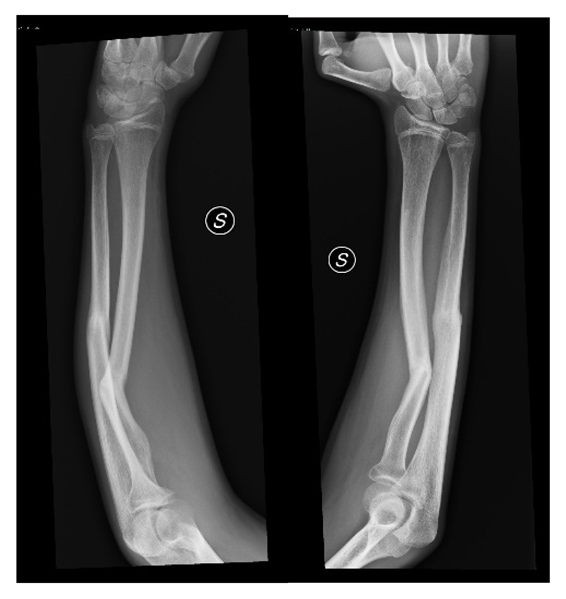

The first step concerns the conversion of tomographic images into a three-dimensional model. As mentioned, the images deduced from the CT are not always appropriately clear to allow the medical specialist to develop in detail the procedure to be performed before the operation, so the process is divided into three main phases in order to emphasize the exact region and create the 3D model, removing unnecessary anatomical parts. Computed tomography is converted to standard triangulation language (STL) to represent the examined anatomy in three dimensions, but the model is too heavy, computationally speaking, and is marked by a dense structure that must be optimized. To do that, MeshLab is used for the elimination of the inner material of no interest and the overlapped geometries, and MeshMixer for external surface and file format correction. The steps of this first part of the workflow are summarized below (in order: Figure 1 is the importation in InVesalius of the CT exam, Figure 2 is the processing to optimize the 3D surface obtained and Figure 3 is the correction of mesh errors.

Figure 1.

Computed Tomography and TC display on InVesalius.